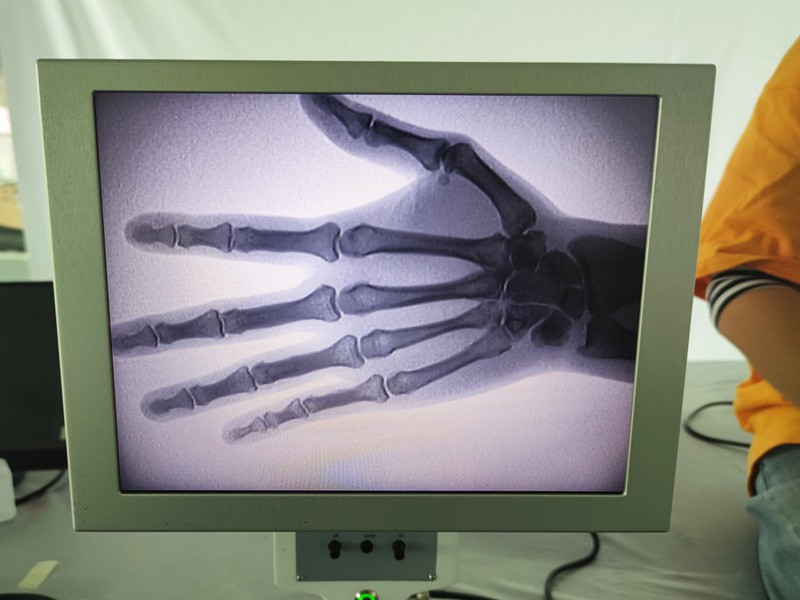

Magna portabbli tar-raġġi X As-c200 hija strument portabbli b'doża żgħira ta 'radjazzjoni u sigura ħafna. Huwa adattat b'mod speċjali għal unitajiet u individwi b'baġit insuffiċjenti u rekwiżiti baxxi għal stampi. Il-ġenerazzjoni l-ġdida hija mgħammra bi skrin kbir ta 'definizzjoni għolja ta' 10 pulzieri, li għandu firxa ta 'perspettiva akbar u jista' jipperspetta bis-sħiħ il-pala kollha. Huwa l-aktar adattat għall-perspettiva ortopedika medika. Jista 'jkun imqabbad ma' printer tal-films biex jistampa films ortopediċi, u jista 'jintuża wkoll fil-produzzjoni u l-ittestjar industrijali. Ebda kamra mudlama, perspettiva diretta, osservazzjoni immedjata, riżoluzzjoni għolja u immaġni ċara.

Il-Magni Ortopediċi tar-Raġġi X tagħna huwa prodott ta 'kwalità għolja li kien iddisinjat partikolarment għall-immaġini ortopediċi. Jista 'jintuża għad-dijanjosi u l-ippjanar tat-trattament ta' kundizzjonijiet ortopediċi varji, inklużi ksur, dislokazzjonijiet, artrite u tumuri fl-għadam. Hija mgħammra b'teknoloġija avvanzata tar-raġġi-X li tippermetti immaġini ta 'kwalità għolja b'espożizzjoni mnaqqsa għar-radjazzjoni. Il-magna għandha sistema ta 'immaġni b'riżoluzzjoni għolja u tista' taqbad immaġini ta 'kwalunkwe struttura tal-għadam b'ċarezza kbira.

3. Wirja ta 'immaġni kbira: Il-magna għandha wirja ta' immaġni kbira, li tipprovdi fluss tax-xogħol effiċjenti u identifikazzjoni faċli ta 'sejbiet kritiċi.